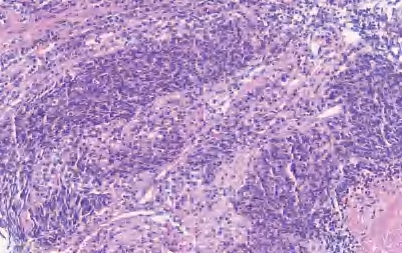

【定义】类癌是恶性LNEN伴分化良好的器官样结构,它包括两类:典型类癌(TC),核分裂<2个/2 mm 2 ,缺乏坏死(图2-13);不典型类癌(AC),核分裂为2~10个/2 mm 2 和(或)坏死,通常为点灶状(图2-14)。

图2-13 TC

【镜下形态】TC和AC为分化好的NET伴有独特的肿瘤结构和细胞学特征。肿瘤细胞为小至中等大小,呈立方形、多角形或梭形(梭形细胞尤其易发生在周围型病变中),形态较一致,核仁不明显,核染色质呈细颗粒状、中至大量嗜酸性颗粒胞质。临床上TC为低级别,AC为中级别,二者的区别在于核分裂象和有无坏死。也可见到嗜酸性颗粒细胞、透明细胞和含色素的类癌。与LCNEC和SCLC不同,伴有SCC或腺癌的复合型类癌不常见。此外,类癌不与SCLC和LCNEC混合存在。罕见的类癌,形态符合不典型类癌,但核分裂象>10个/2 mm 2 或Ki-67增殖指数偏高(>30%),有限的病例基因学分析显示其与类癌关系密切,而不是SCLC和LCNEC(缺乏RB1或TP53基因突变,低的总肿瘤负荷或MEN1基因突变的存在)。类癌肿瘤细胞呈低分子CK阳性,高分子CK阴性;神经内分泌标记CgA、Syn、CD56、INSM1呈强阳性。周围型肿瘤TTF-1呈阳性,中央型肿瘤TTF-1呈阴性。尽管Ki-67增殖指数>5%更可能是AC,但Ki-67的增殖指数不是肺类癌的诊断标准,尤其在TC与AC的鉴别中。Ki-67的主要作用是在挤压的细胞学或小活检中排除SCLC或LCNEC。